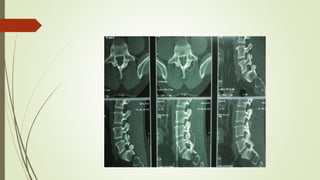

 SPECT (single photon emission computed tomography)

shows area of involvement

DIAGNOSTIC PROCEDURE  SPECT(single photon emission computed tomography) shows area of involvement  X-ray shows area of involvement